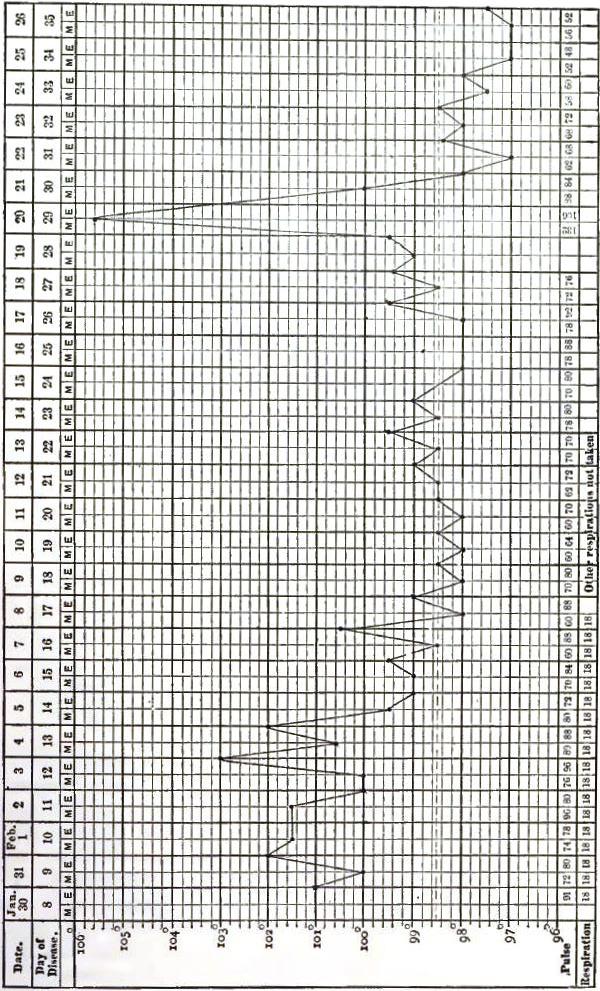

| 17. | CHART OF TEMPERATURE IN TYPHOID FEVER WITH RELAPSE.—RELAPSE |

| 18. | TEMPERATURE CHART OF TYPHOID FEVER.—ABORTIVE ATTACK, FOLLOWED BY TYPICAL ATTACK |

| 19. | SPIRILLUM FROM THE BLOOD IN A CASE OF RELAPSING FEVER |

| 20. | TEMPERATURE CHART OF TYPICAL CASE OF RELAPSING FEVER, WITH THREE RELAPSES TERMINATING IN RECOVERY |

| 21. | TEMPERATURE CHART OF TYPICAL CASE OF RELAPSING FEVER, TERMINATING IN RECOVERY |

Of all these manifold evidences of fever, the elevation of temperature is the one whose cause, range, and results have been most carefully and critically investigated. No record of a case in which fever is present is regarded as complete without the chart of the daily variations in temperature, respiration, and circulation. The practical value of such records is thus admitted, and in the experiments relating to the origin of animal heat the observations of temperature are as essential as the chemical analyses, each of which supplements the other.